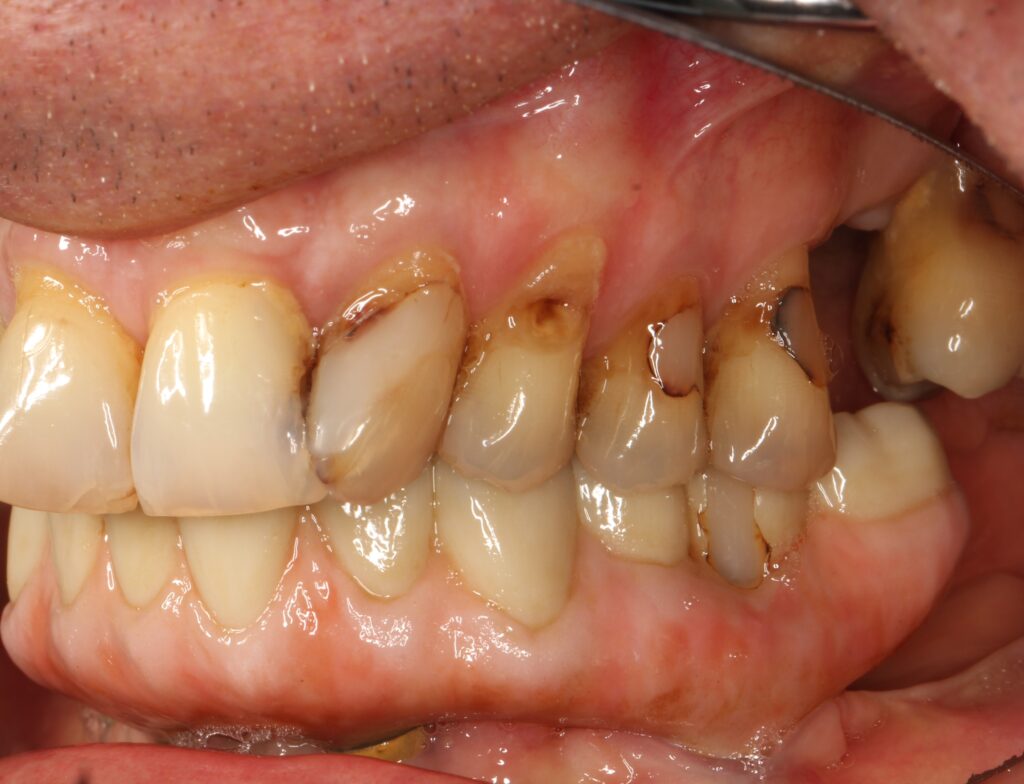

A selection of full arch fixed implant bridge patients after 5 years of wear